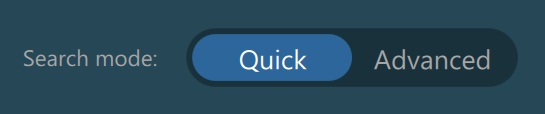

Search Mode¶

The VisioVIEW software allows users the choice of their preferred mechanism when browsing the Study List and the PACS database by offering a Quick and an Advanced search mode. Select the default active search mode on application startup

through the VisioVIEW settings.

Quick Search¶

Users can easily search studies by using the Quick Search input field located in the Study Browser toolbar, or using the Home Screen’s search bar.

The Quick Search input field filters out the studies by matching either the patient name, owner name, or patient ID parameters. The Study List is automatically filtered as soon as the user starts typing into the field, after the initial

filter timer has elapsed.

To clear the active filter, click the x icon at the end of the input fields.

Advanced Search¶

Activate the Advanced search mode from the Study Browser toolbar to access the available options. The same panel can also be accessed on the Home Screen as well.